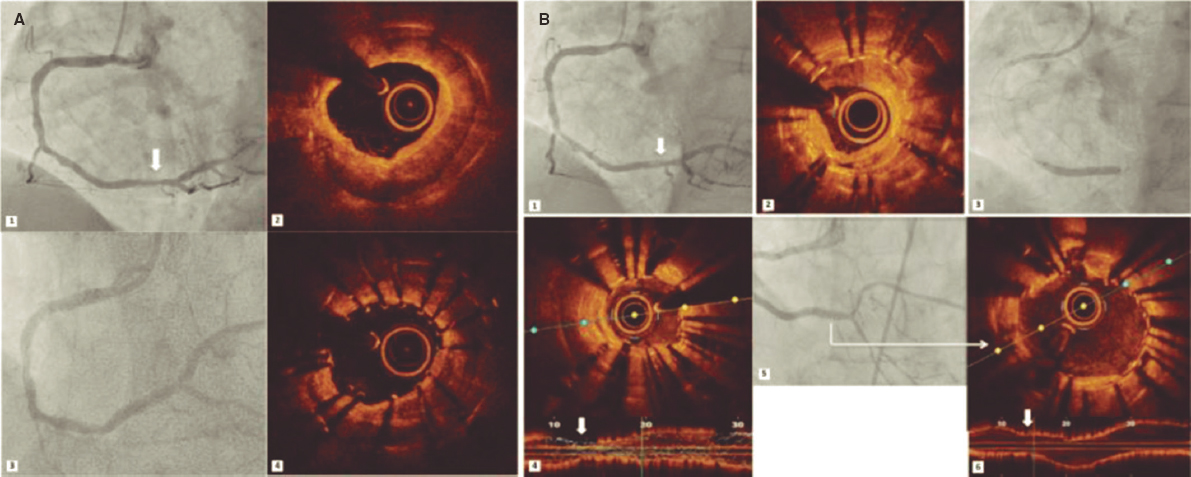

A 48-year-old woman with congenital pulmonary stenosis who required surgical valvuloplasty in 1978 presented with progressive dyspnea. The cardiovascular magnetic resonance imaging performed confirmed the presence of dilated right ventricle, severe regurgitation, and pulmonary artery aneurysm (39 × 25 mm). The heart team decided to perform a transcatheter pulmonary valve implantation. During pre-stenting with an uncovered 15-25 mm × 47-55 mm CP Stent (NuMED, United States) mounted on a 25 mm balloon of the native right ventricular outflow tract, stent embolization with spontaneous anchoring to the left pulmonary artery occurred (video 1 of the supplementary data, and figure 1A). Since the patient remained stable, a wait-and-see approach was decided to facilitate stent endothelialization. The stent (figure 1B) was used as the anchoring substrate 2 months apart of the proximal implantation for 2 longer Andrastent XXL 57 mm-stents (Andramed, Germany) on a 30 × 40 mm XL AndraBalloon to create a landing zone for the 29 mm Sapien-3 valve. The rest of the procedure was successful (figure 1C). The patient remained asymptomatic, with no perfusion defects as confirmed by the ventilation/perfusion lung scan and a mean transvalvular gradient of 7 mmHg without any residual regurgitation at the 6-month follow-up (figure 1D).

Figure 1.

In cases of aneurysmal pulmonary trunk and dilated native/non-calcified right ventricular outflow tract, the high risk of stent or valve migration may be prevented by the “planned” implantation of a first stent of smaller dimensions in a pulmonary branch. Then, sequential proximal stents may be anchored to this landing zone, which facilitates the reconstruction of pulmonary trunk with low risk of flow compromise in the jailed pulmonary branch. Further studies to assess this scenario are warranted.